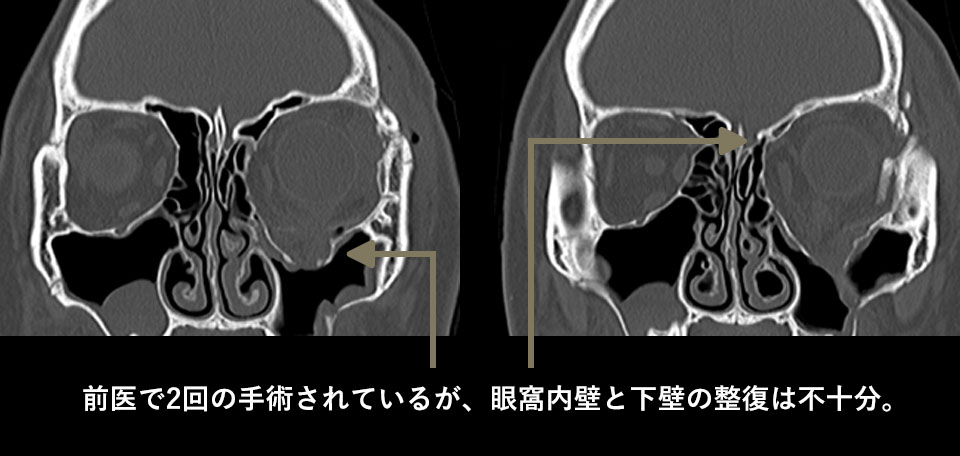

B大学病院で2回手術をされていますが、左眼の重度の眼球陥凹が残存しており、左右非対称の顔貌となってしまっています。また下眼瞼へなぜか脂肪移植されているためこれも左右差を助長する原因となっています。

CTでは再建手術を2回されているものの、骨壁を治すことが出来ていないため、眼窩の断面積が縮小していません。これが眼球陥凹の大きな原因でした。